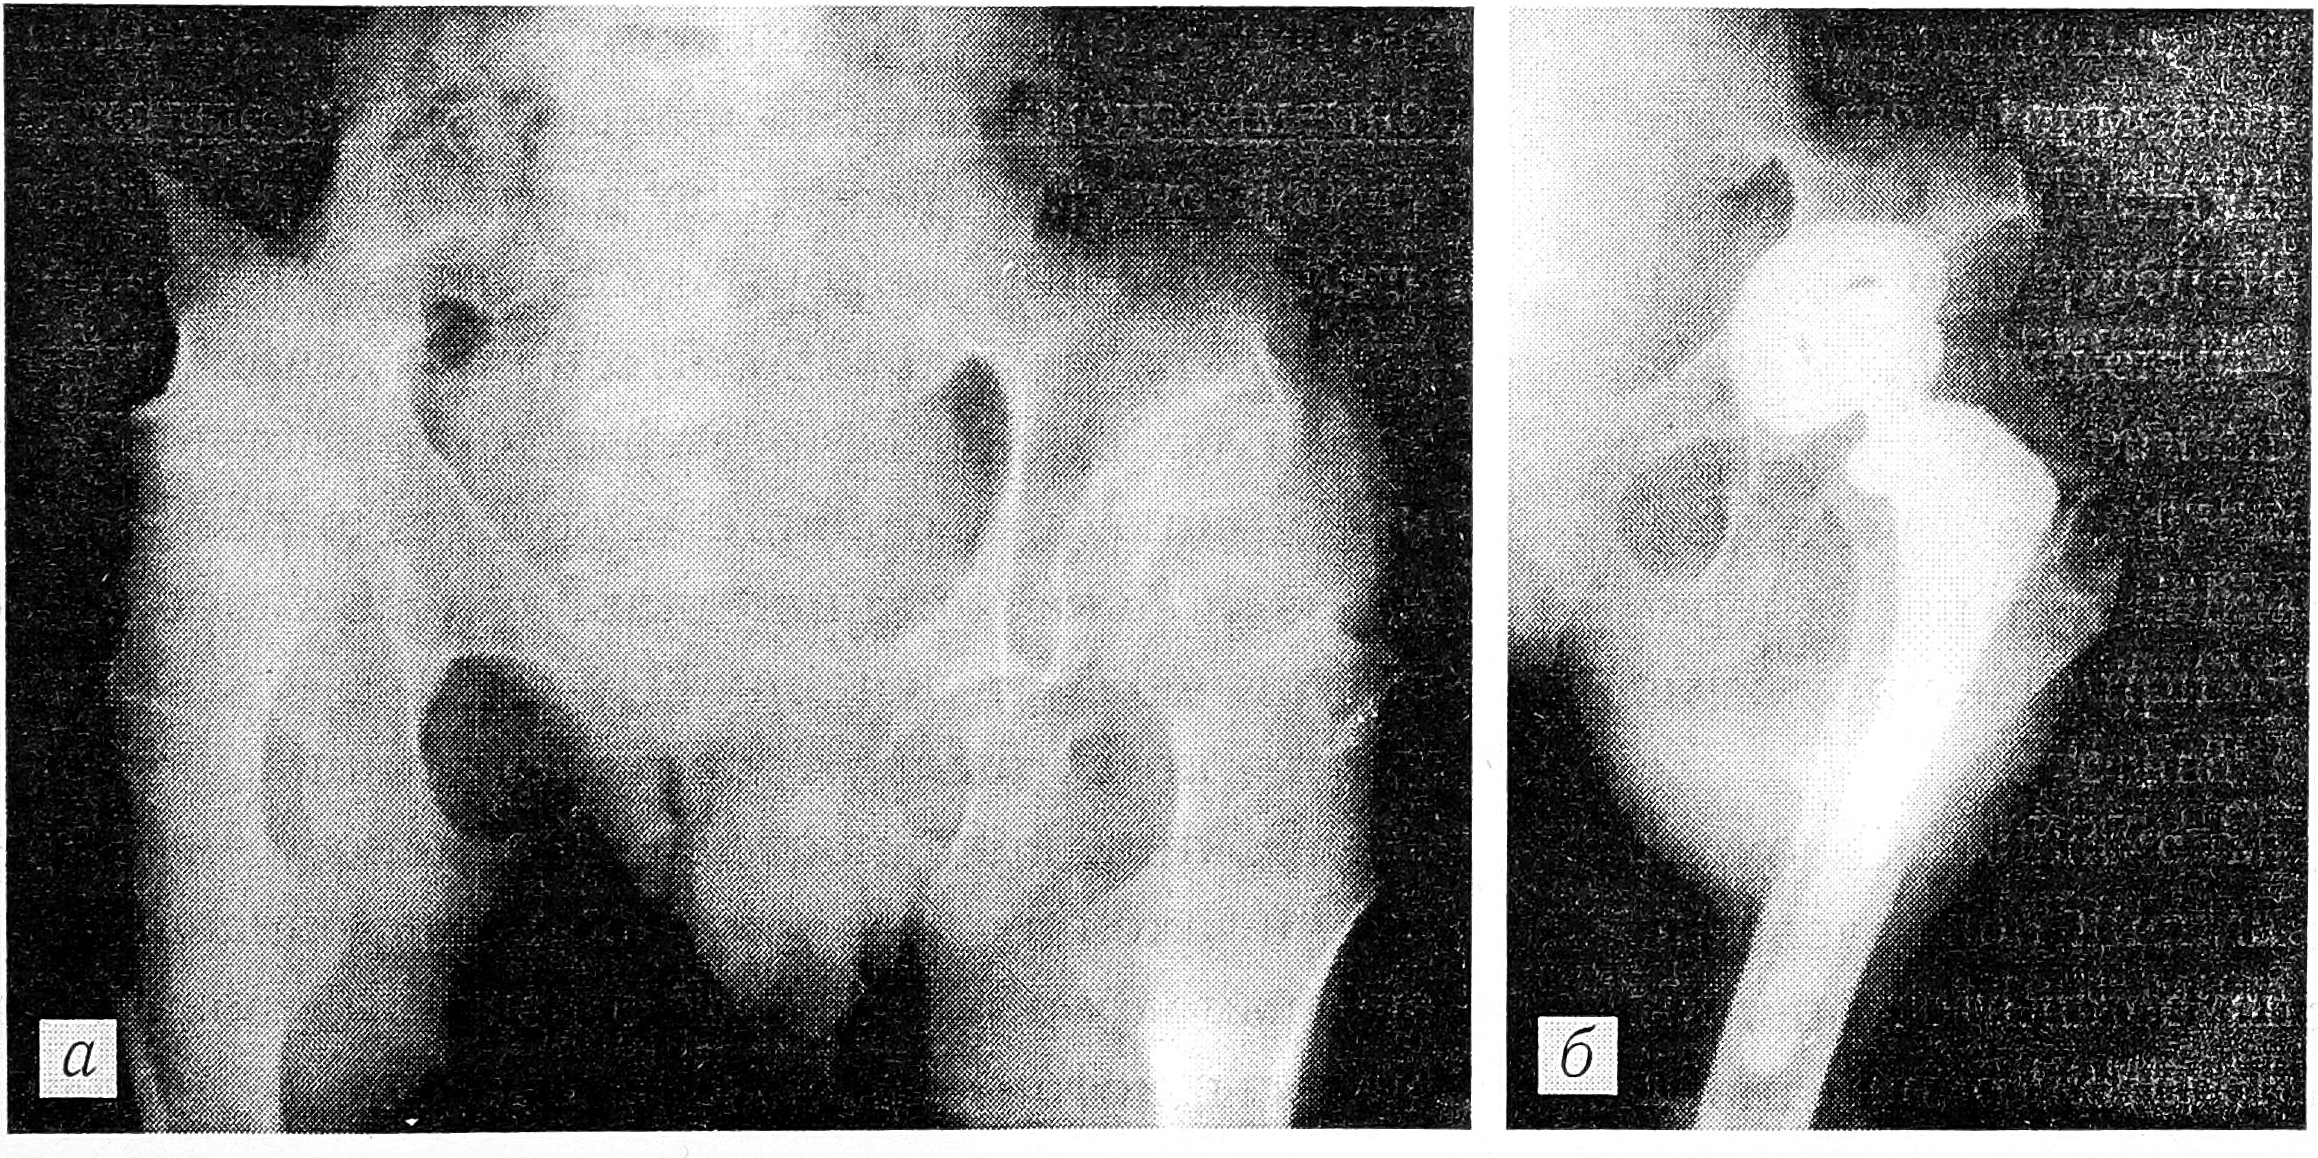

У подростков 14—16 лет проводится третий этап хирургического лечения: выполняются операции, типичные для второго этапа, и артропластика. Применение артропластики с биологическими прокладками не оправдало себя из- за быстрого рубцевания тканей и потери амплитуды движений через 1—2 года после операции. При поражении тазобедренных суставов и позвоночника, двустороннем коксартрозе III стадии или анкилозе в порочном положении, а также при сочетании поражения тазобедренного сустава с патологией других суставов у больных с множественной и спондилоэпифизарной дисплазией операцией выбора является тотальное эндопротезирование (рис. 3), применение которого улучшает медицинскую, социальную реабилитацию и психологическую адаптацию пациентов. Однако эндопротезирование у детей должно быть строго обосновано, и не только медицинскими, но и социальными показаниями с учетом будущей профессии и образа жизни больного [4].

Рис. 3. Рентгенограммы подростка, страдающего спондилоэпифизарной дисплазией, с двусторонним фиброзным анкилозом тазобедренных суставов в порочном положении до (а) и после (б) эндопротезирования левого тазобедренного сустава эндопротезом «Biomet».